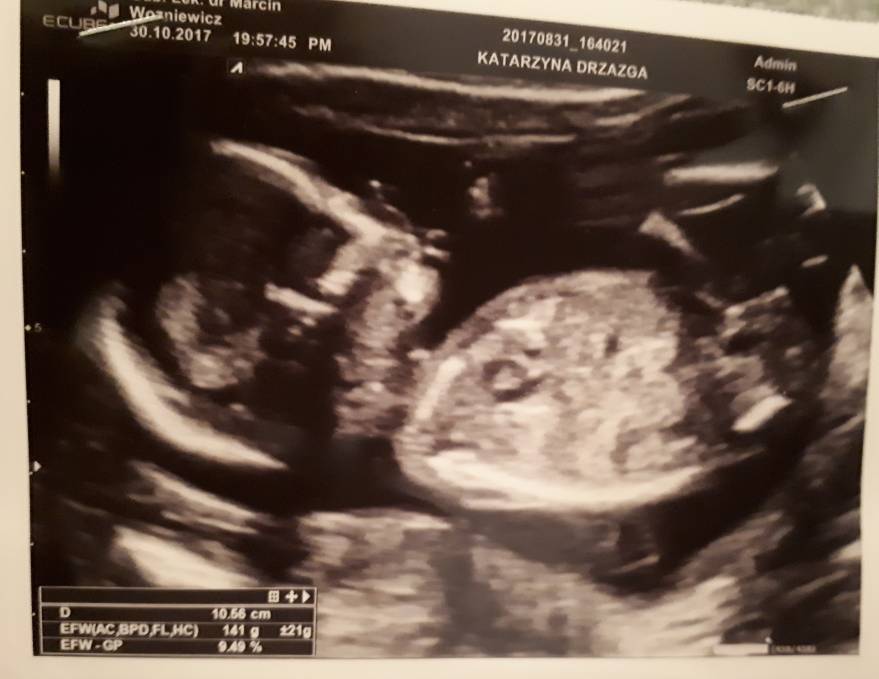

Hej. Ja właśnie po wizycie jakaś mala ta moja DZIEWCZYNKA 10.56cm waga 141g różnica między USG a OM jest ponad tydzień. Będę miałam drugie CC narazie celibat na sex. Łożysko przodujace